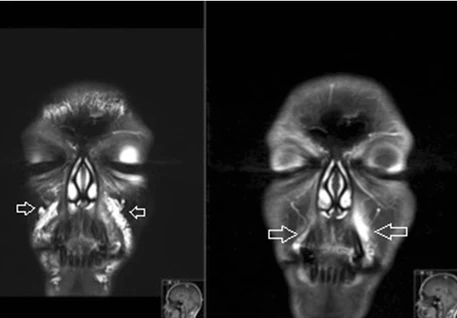

Clinical imaging has identified HA fillers well beyond typical marketing windows:

• MRI/US detection of filler in patients up to 2, 6, 10+ years after injection; periocular regions are frequent sites of persistence and migration.

MRI visualization of facial dermal filler deposits

Representative MRI identifying facial filler deposits (e.g., Tal et al., 2016).